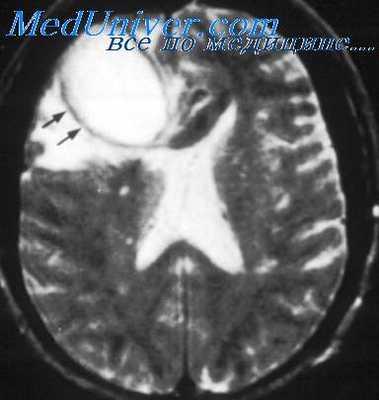

- Нейровизуализация. Для исключения отека или мозгового новообразования, а также при подозрении на осложненное течение менингита показана КТ головного мозга. Для более детального изучения структуры мягкой мозговой оболочки проводится МРТ головного мозга.

- КТ или МРТ головного мозга. Исследования дают возможность четко визуализировать локализацию абсцессов или очагового энцефалита, определить их размеры, выявить перифокальный отек, дислокацию и деформацию желудочков мозга. Контрастные методики показаны при подозрении на тромбоз кавернозного или сигмовидного синуса.